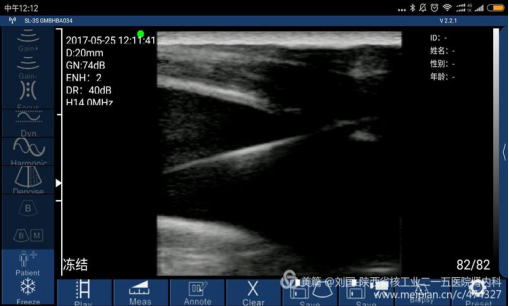

case 3:索诺星无线超声经WiFi连接小米max,同步引导带cuff的颈内静脉留置导管的置入

使用mini无线超声(索诺星)的几点体会:

1.使用前最好关闭手机上运行的APP软件,确保超声软件的运行;

2.因为系WiFi连接,手机作为显示器,图像传输存在一点时滞,所以当显示不理想时,要缓慢移动超声探头,不要操之过急,否则难以获取满意的影像;

3.无意中发现用碘伏和盐水作为耦合剂时,效果差异让人诧异,用盐水吧!

4.由于没有彩色频谱,所以不能依此判断动、静脉;但是,也不能单凭能否压瘪作为判断动、静脉的依据,应该结合物理查体等,尤其是消瘦的患者,特别要注意。我有前车之鉴哦!